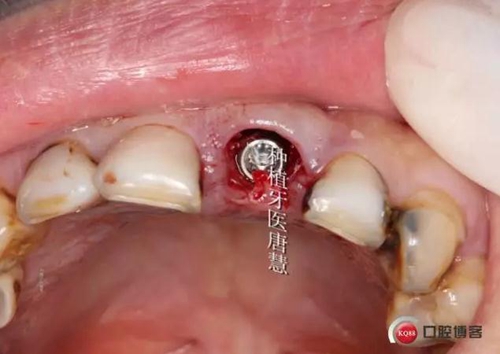

口內(nèi)情況

于殘根偏腭側(cè)備洞